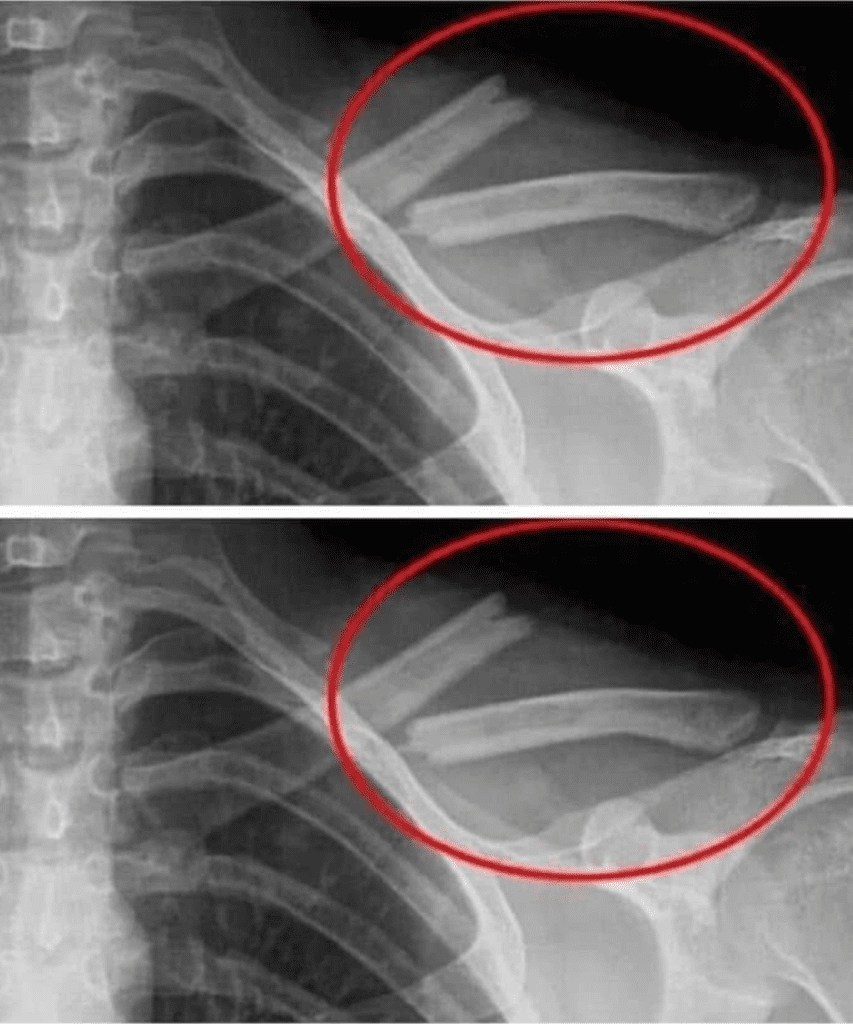

1. SOFT DRINKS + SOFT BONES + OSTEOPOROSIS

If you don’t want to have to depend on calcium supplements all your life, regulate your soda intake immediately. It greatly weakens the basic skeleton that our form depends on, leading to a lot of joint pain and other detrimental health damages.